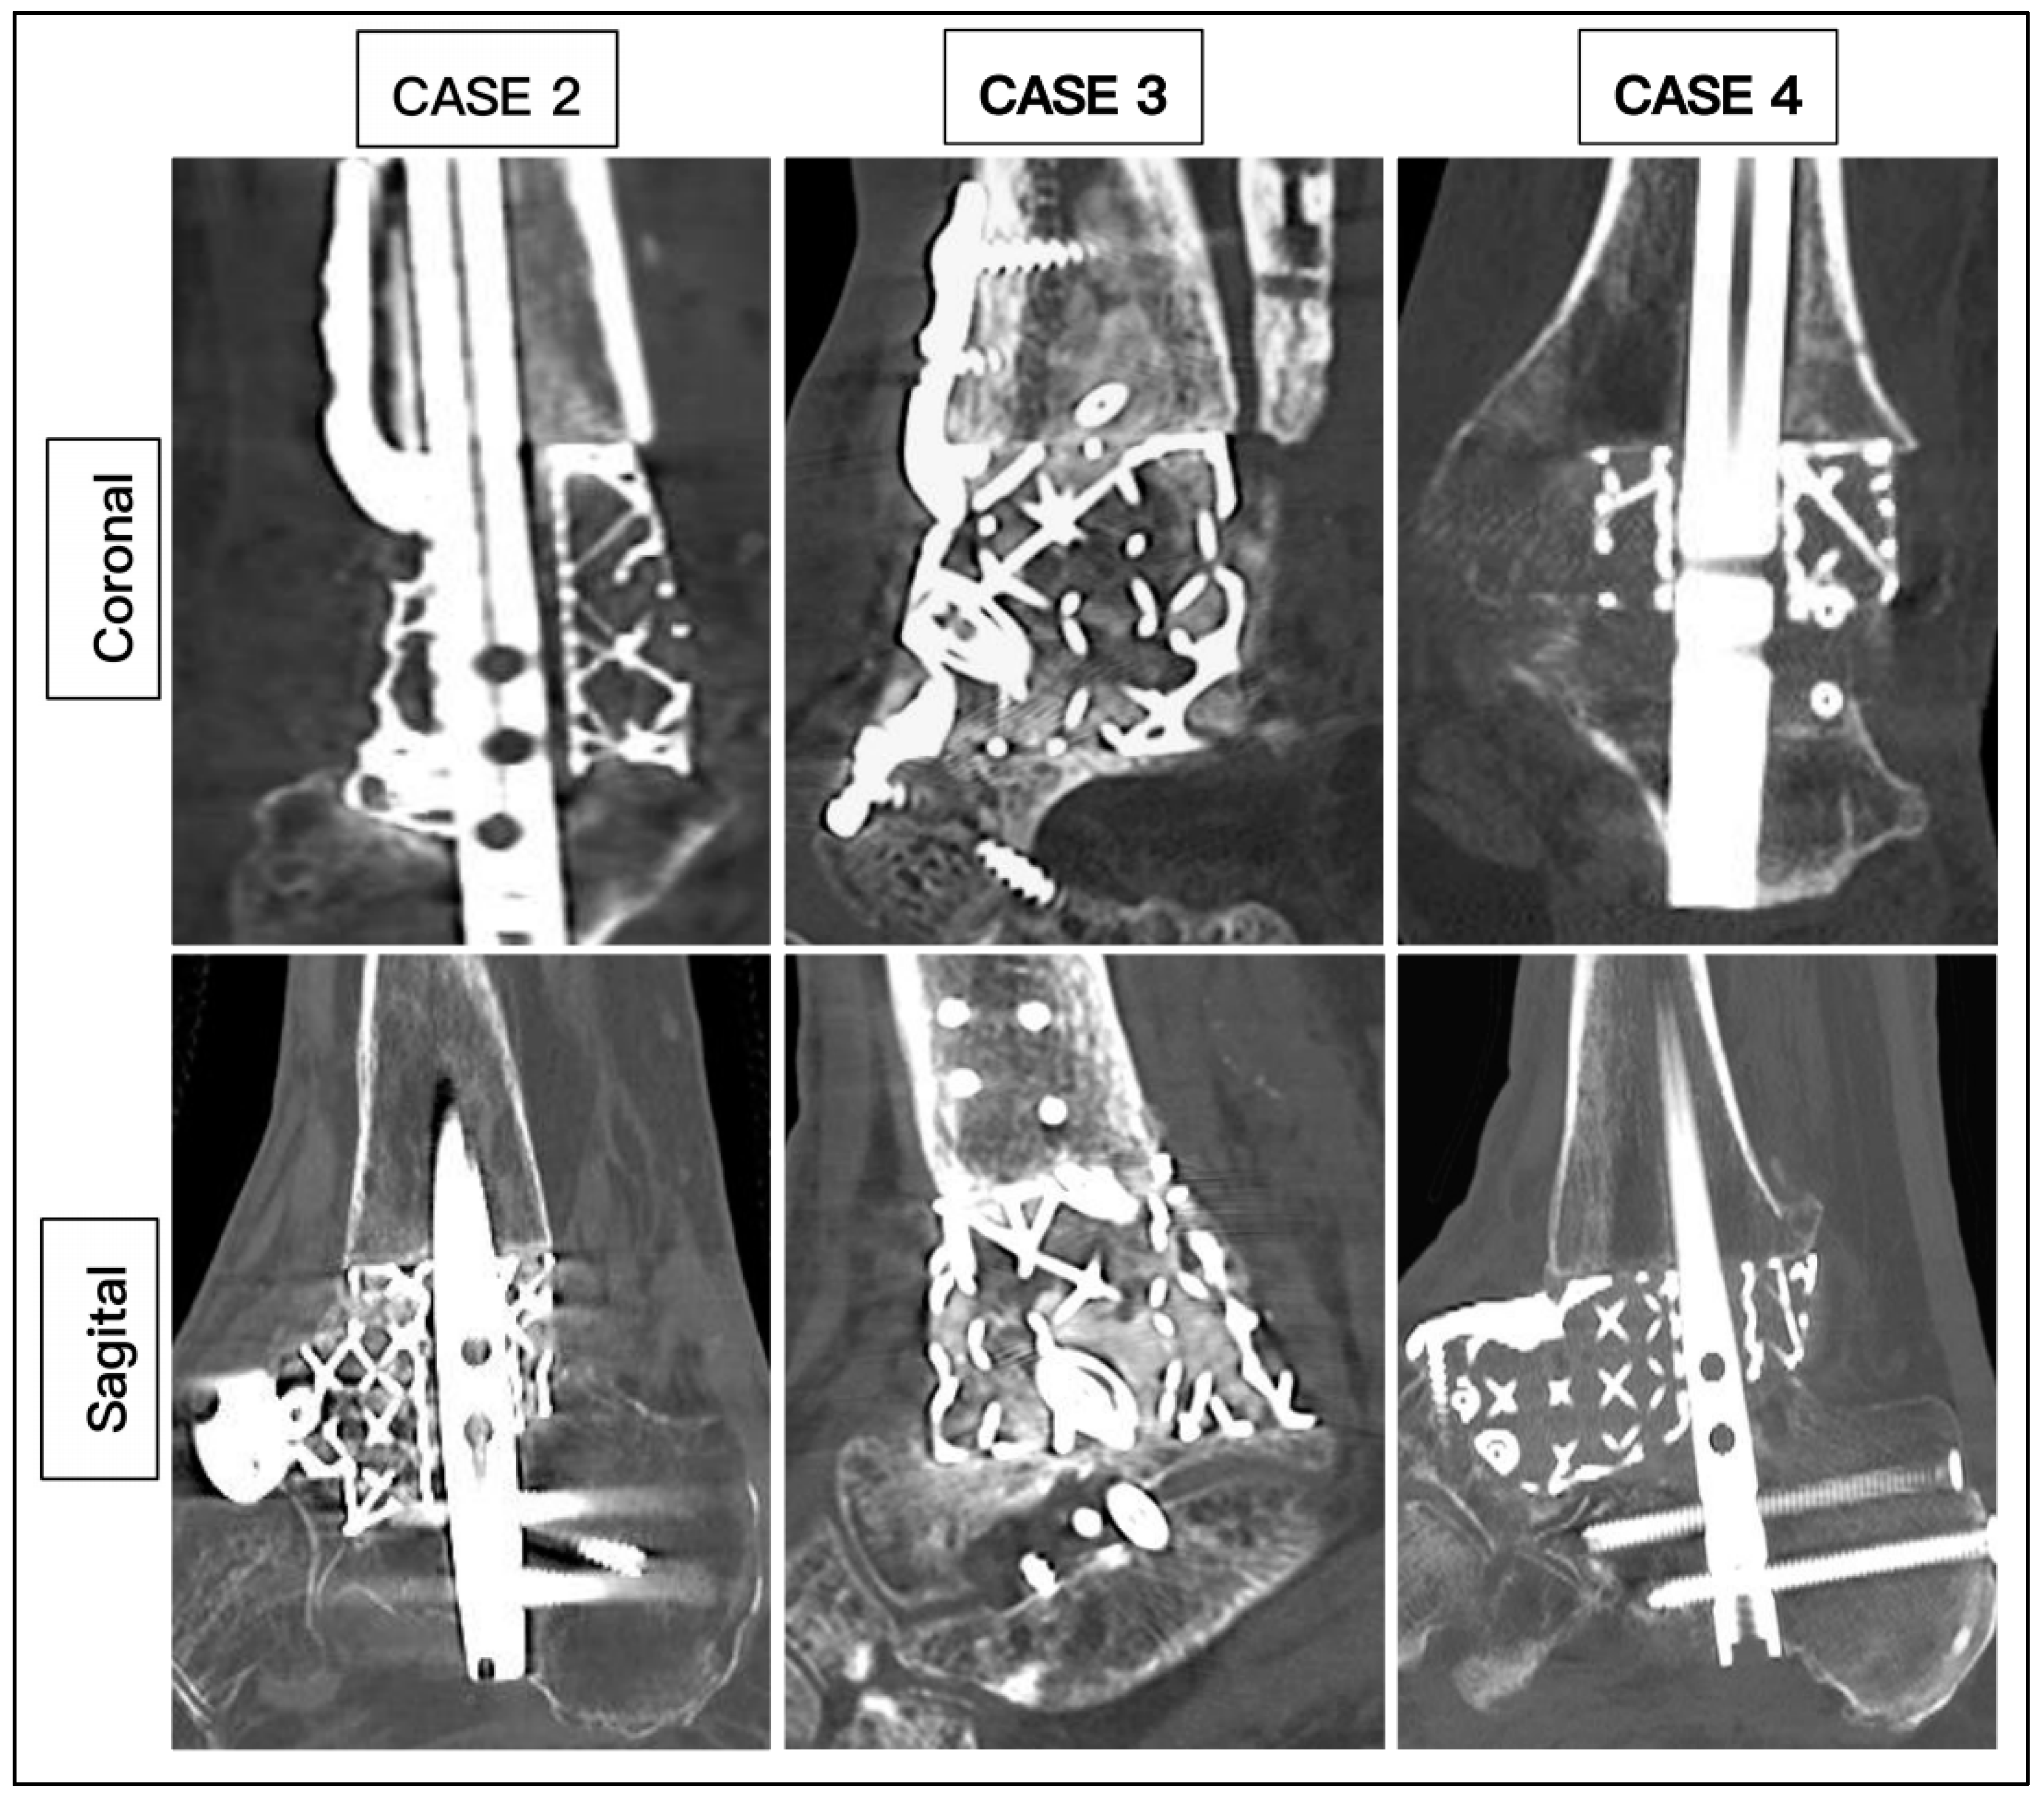

3. Results